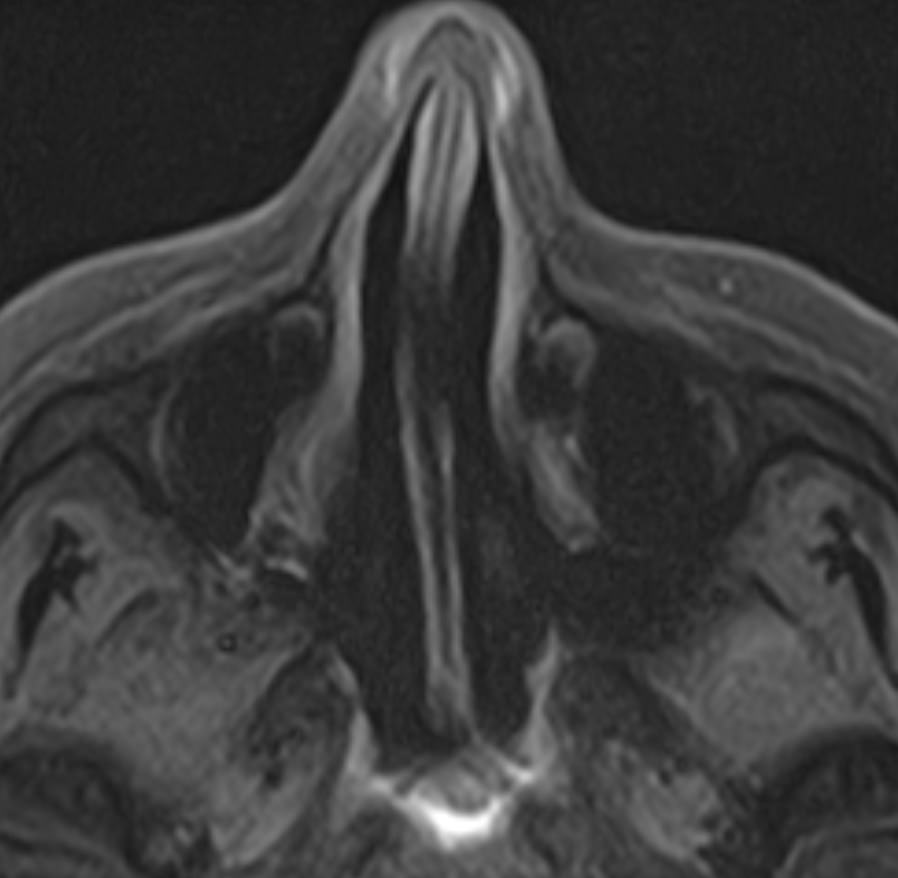

Придаточные пазухи носа представляют собой воздухоносные полости, которые располагаются в костях лицевого и мозгового черепа, выстланы изнутри слизистой оболочкой и сообщаются с полостью носа. МРТ является неинвазивным безопасным информативным способом визуализации данных анатомических областей. Метод позволяет диагностировать различные патологические процессы в области придаточных пазух носа.

Реализацию МРТ пазух носа предписывают, когда другие способы обследования больного не дают полную диагностическую картину. Это необходимо, когда нужны данные о состоянии сложно доступных клиновидных или решетчатых пазух, расположенных за костно-хрящевыми структурами черепа.

Снимки, полученные в ходе магнитно-резонансной томографии, дают подробные данные о:

• патологиях формирования пазух и полости носа;

• аномалиях строения костно-хрящевых структур;

• утолщениях костных стенок и слизистых оболочек;

• степени симметричности околоносовых полостей;

• скоплении крови или иных жидкостей в придаточных пазухах носа.